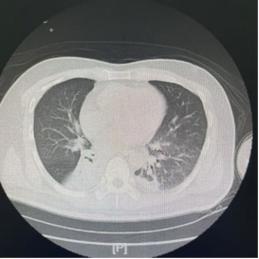

- 行动要果断: 一旦发现上述信号,必须立即通知医生,进行血常规、C反应蛋白、胸部X光或CT等检查,明确诊断并尽早开始强有力的抗感染治疗,早期使用敏感抗生素,是控制感染、防止病情恶化的基石。